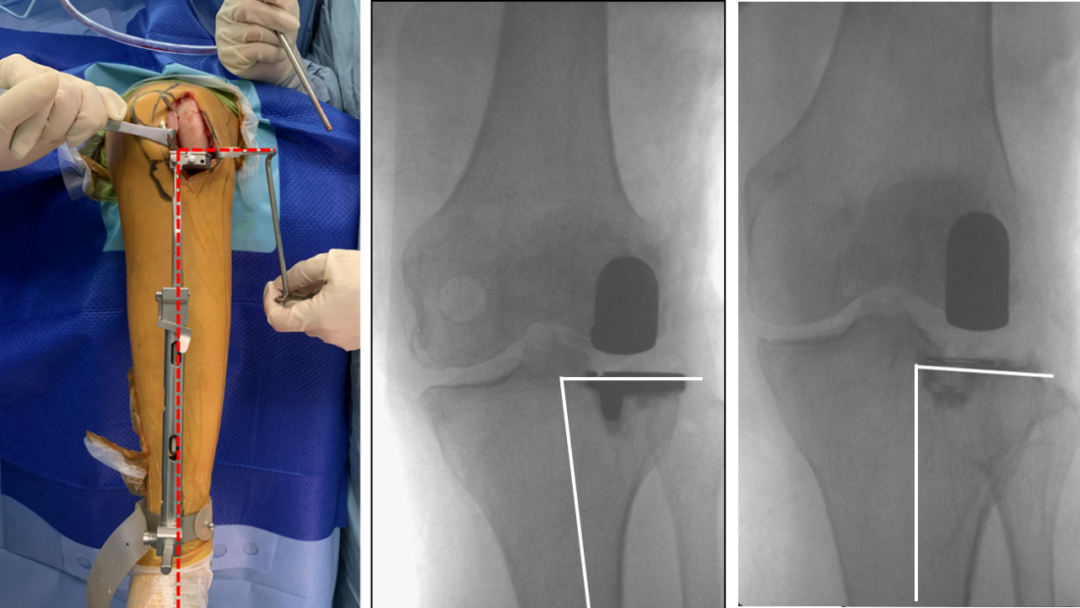

术前透视片

四、术后X透视片